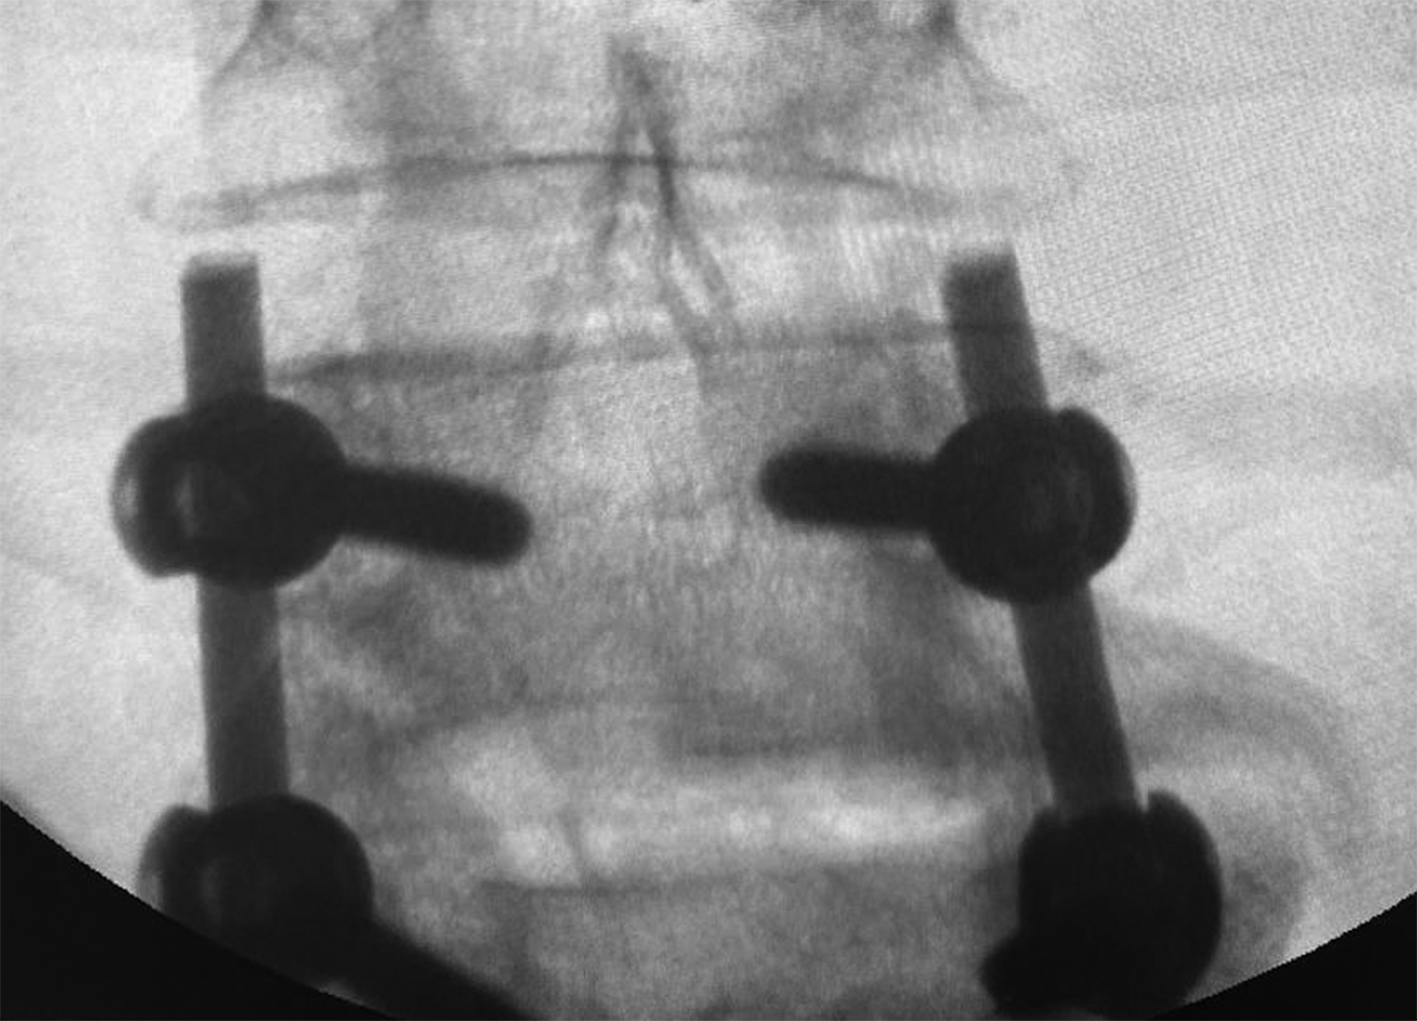

The patient underwent surgical intervention, including transpedicular fixation of the spine at the L4/L5 level and removal of the herniated intervertebral disc at L4/L5 (Fig. 1). In the postoperative period, the patient reported a reduction in pain in the right thigh; however, pain persisted in the sacrococcygeal region and the lower lumbar spine. Postoperative pain assessment using VAS was recorded at 7 cm.

Fig. 1. Intraoperative radiographic control image of the lumbar spine in the anteroposterior view. The transpedicular fixation system is installed at the L4/L5 level